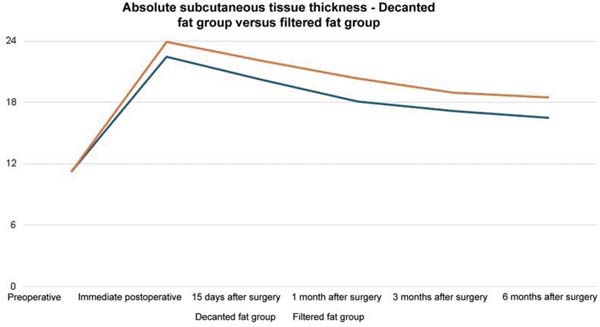

The average volume of fat grafted was 116.7 mL in the decanted graft group and 123.3 mL in the filtered graft group. The average initial thickness of the subcutaneous tissue was approximately 11 mm in both groups. This value increased to 22 mm in the immediate postoperative period in the decanted group and 23 mm in the filtered group.

Both groups presented progressive reabsorption. ►Table 1 and ►Fig. 5 show the change in mean subcutaneous thickness in both groups.

In the decanted graft group, the average reduction compared with the initial thickness after lipofilling was 9.90% on day 15, 19.27% on month 1, 23.59% on month 3, and 26.36% on month 6. In the filtered graft group, the average reduction compared to the initial thickness after lipofilling was 7.74% on day 15, 14.85% on month 1, 20.67% on month 3, and 22.80% on month 6 (►Fig. 6). ►Figs 7–8 reveal the ultrasound change in subcutaneous tissue’s thickness before and after lipofilling. ►Figs. 9–10 show the pre-and postoperative results of one patient from each group.

The comparison of subcutaneous thickness reduction at 6 months between the graft decantation and filtration techniques showed no statistically significant difference (p ¼ 0.59).